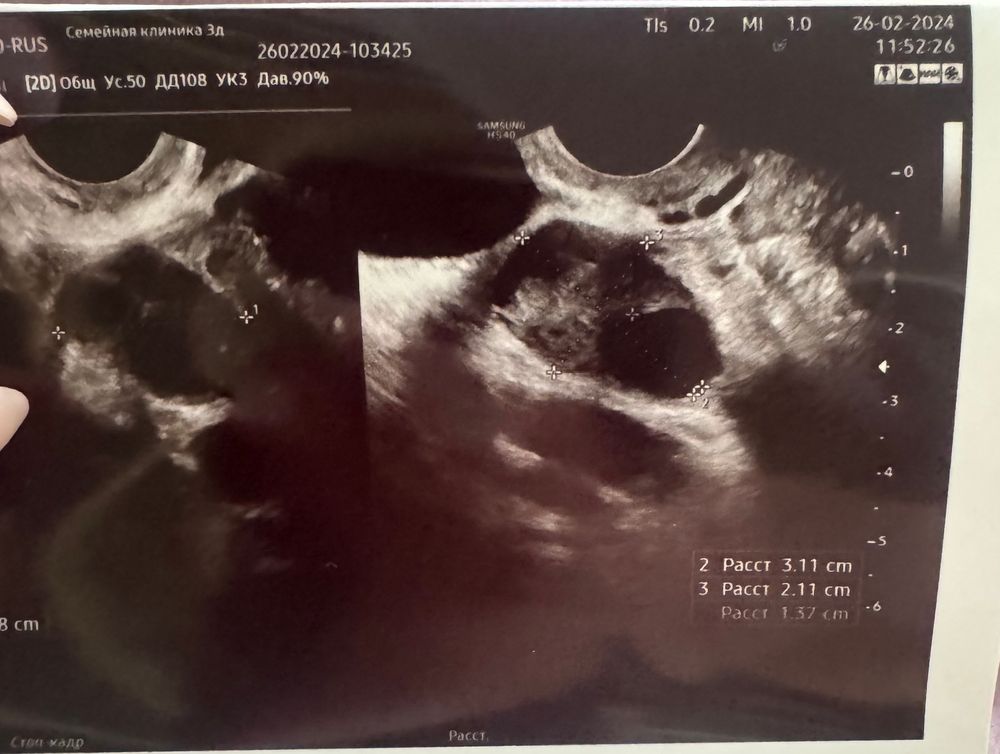

10 дц на узи фолликул 13,7 мм. Это доминантный фолликул ? Овуляция обычно поздняя на 18-19 дц. На какой день цикла ждать приблизительно О в этом цикле?

эндометрий 8,1 не толстый ли ?

Примерно через 5-6 дней, фолик растёт по 2 мм в день и лопается при размере 21-24 мм.

С таким размером фолликула, овуляция и через 3 дня может наступить, и через 6. В любом случае, нужно скоро начинать стараться через день, тогда не пропустите овуляцию.

Аня, да сегодня уже начнем 🙏 особо не надеюсь , так как по узи есть эндометриодная киста. Спасибо большое за ответ 🙏❤️